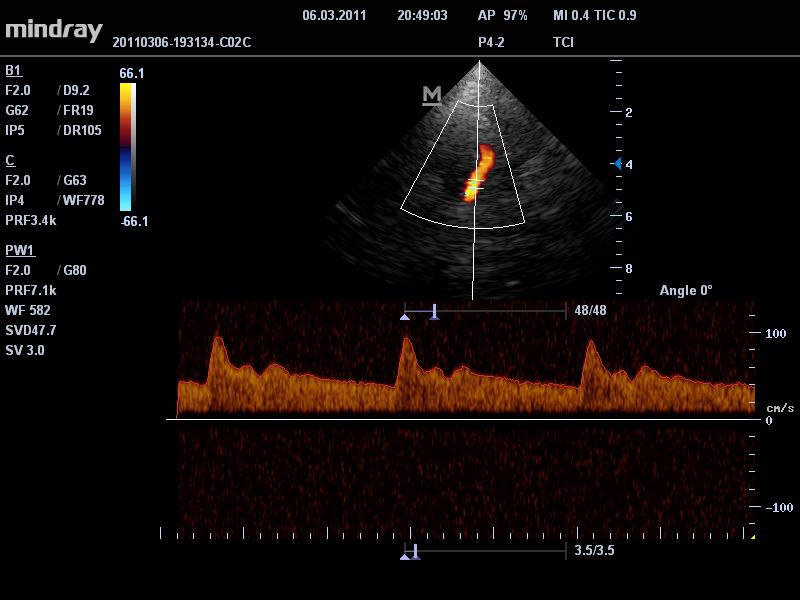

УЗИ-аппарат

Mindray DC-T6

Ультразвуковая система Mindray DC-T6 – это инновационный аппарат для проведения высокого уровня диагностики с качественной визуализацией и широким спектром применения. Платформа рекомендована для использования в коммерчески многопрофильных медицинских учреждениях и государственных лечебных клиниках.

• Режимы сканирования: B/M/CFM/PDI/Направленный PDI/PW, HPRF, Тканевая гармоника, М- и цветной М-режим.